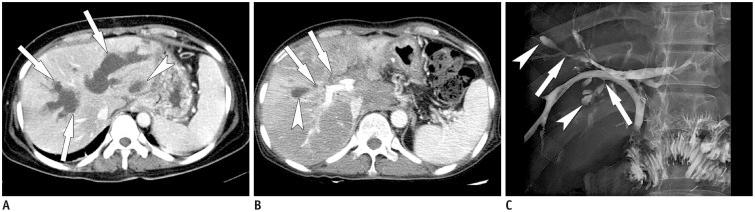

Sclerosing cholangitis is a spectrum of chronic progressive cholestatic liver disease characterized by inflammation, fibrosis, and stricture of the bile ducts, which can be classified as primary and secondary sclerosing cholangitis. Primary sclerosing cholangitis is a chronic progressive liver disease of unknown cause. On the other hand, secondary sclerosing cholangitis has identifiable causes that include immunoglobulin G4-related sclerosing disease, recurrent pyogenic cholangitis, ischemic cholangitis, acquired immunodeficiency syndrome-related cholangitis, and eosinophilic cholangitis. In this review, we suggest a systemic approach to the differential diagnosis of sclerosing cholangitis based on the clinical and laboratory findings, as well as the typical imaging features on computed tomography and magnetic resonance (MR) imaging with MR cholangiography. Familiarity with various etiologies of sclerosing cholangitis and awareness of their typical clinical and imaging findings are essential for an accurate diagnosis and appropriate management.

硬化性胆管炎是一种慢性进行性胆汁淤积性肝病,其特征为胆管炎症、纤维化和狭窄,可分为原发性硬化性胆管炎和继发性硬化性胆管炎。原发性硬化性胆管炎是一种病因不明的慢性进行性肝病。另一方面,继发性硬化性胆管炎有可识别的病因,包括免疫球蛋白G4相关硬化性疾病、复发性化脓性胆管炎、缺血性胆管炎、获得性免疫缺陷综合征相关胆管炎和嗜酸性胆管炎。在本综述中,我们基于临床和实验室检查结果以及计算机断层扫描和磁共振(MR)成像(包括MR胆管造影)的典型影像学特征,提出一种系统性的硬化性胆管炎鉴别诊断方法。熟悉硬化性胆管炎的各种病因并了解其典型的临床和影像学表现对于准确诊断和恰当处理至关重要。